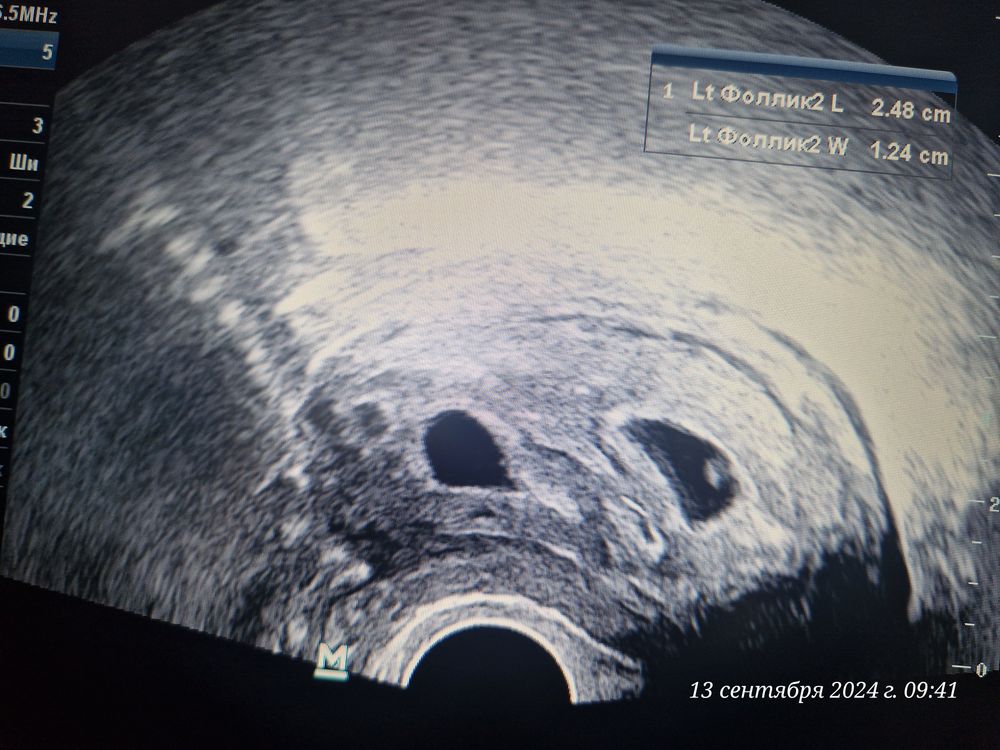

21 дпп. 5н 3д. Оба два 😍

Беременность✏️21 дпп - 13.09.24 Ну вот и состоялось первое наше УЗИ, уже такие большие бусинки😍 Не знаю зачем, но вчера сдала ХГЧ, просто так наверное или просто убедиться, что оба со мной🙏🏻 Результат оказался 37 303 МЕ/л не ожидала такой увидеть.

Диаметр первого ПЯ - 14 мм. ЖМ - 3,5 мм. Хорион до 4,8 мм

Диаметр второго ПЯ - 13 мм. ЖМ - 3.5 мм. Хорион до З,6 мм